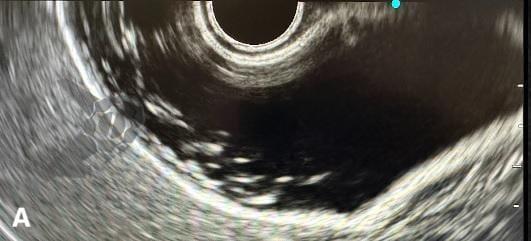

A poeira biliar foi definida como imagem flutuante hiperecogênica, sem sombra acústica posterior, observada ou acentuada após palpação abdominal³. Trata-se, portanto, da mesma entidade ecográfica que, no Brasil, vinha sendo tradicionalmente denominada “microlitíase”, mas que não se enquadra na definição do consenso internacional de microlitíase e acabou sendo praticamente ignorada pelo consenso — ou, em alguns casos, forçadamente incluída sob o amplo guarda-chuva do termo “barro biliar”.

A poeira biliar (“biliary dust”) foi definida como imagem flutuante hiperecogênica, sem sombra acústica posterior, observada ou acentuada após palpação abdominal — entidade ecográfica previamente denominada “microlitíase” ou “microcálculo” em nosso meio. A introdução desse termo visa conciliar os achados ecográficos frequentemente observados na prática diária com as definições estabelecidas pelo Consenso Internacional de 2023.